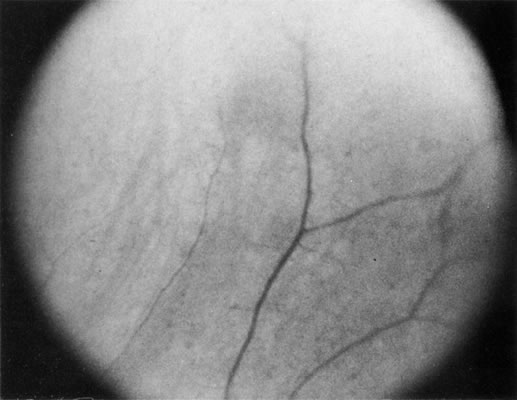

Necrotic melanomas account for approximately 5% of uveal melanomas; in the majority of cases, there is intraocular inflammation accompanying the cataract.7–9Figures 1 and 2 demonstrate a typical case. The patient had a long history of unilateral decreased vision. The eye had become painful 1 month before admission, and he was referred for evaluation of uveitis. Clinically, there was a dense, unilateral cataract with significant intraocular inflammation, which was manifested as a ciliary flush with 2+ cells and flare. Media opacity obscured all fundus detail. An immersion B-scan demonstrated a large intraocular tumor that was most consistent with a uveal melanoma. The eye was removed, and the diagnosis was confirmed histologically.10

Fig. 1. A unilateral media opacity in an adult, requiring that either a foreign body or an intraocular tumor be ruled out. The finding of a large episcleral (“sentinel”) vessel was consistent with either an intraocular tumor or an inflammation. An immersion B-scan helped determine the diagnosis (see Fig. 2).